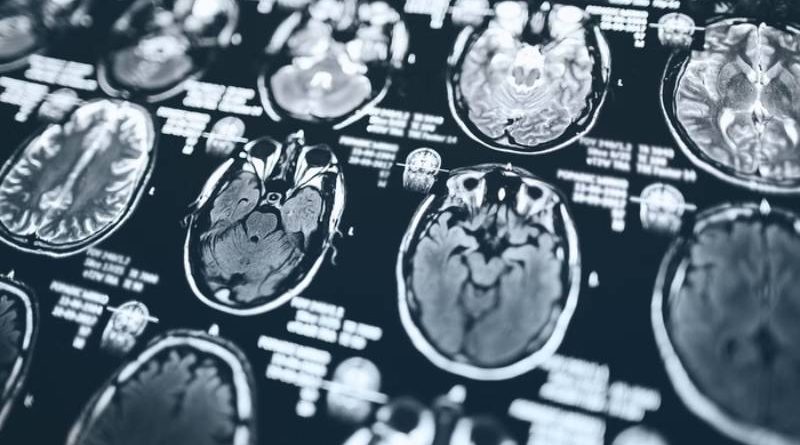

Idosos, homens e pessoas com baixa renda ou desempregadas foram os que tiveram o envelhecimento do cérebro mais evidente durante a pandemia/Foto: Popartic/Getty Images

A pandemia da Covid-19 causou prejuízos à saúde que vão além dos sintomas respiratórios. Um novo estudo mostra que mesmo os cérebros de pessoas saudáveis, que não foram infectadas pelo coronavírus, envelheceram mais rápido do que o esperado durante o período pandêmico.

A pesquisa foi publicada nessa terça-feira (22/7), na revista científica Nature Communications. Cerca de mil pessoas passaram por exames de imagem cerebral e testes cognitivos para que os pesquisadores do Reino Unido pudessem entender melhor os efeitos da pandemia.

Eles descobriram que os cérebros das pessoas que passaram pela pandemia, independentemente de terem sido diagnosticadas com Covid ou não, envelheceram em média 5,5 meses mais rápido do que o esperado.